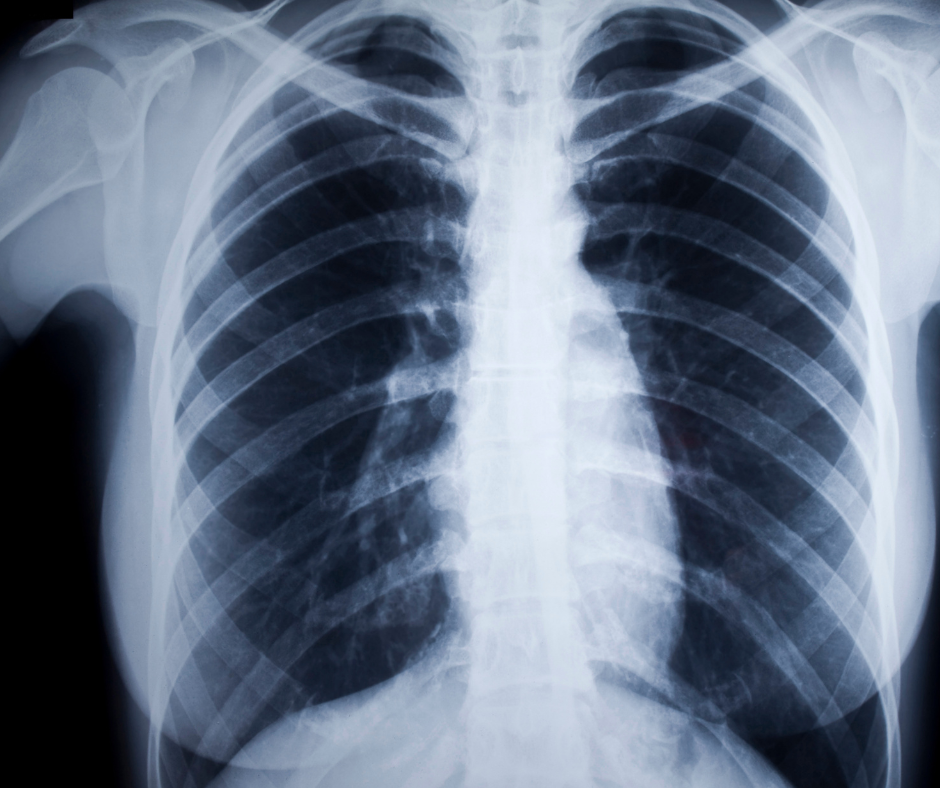

X-Ray

X-RAY